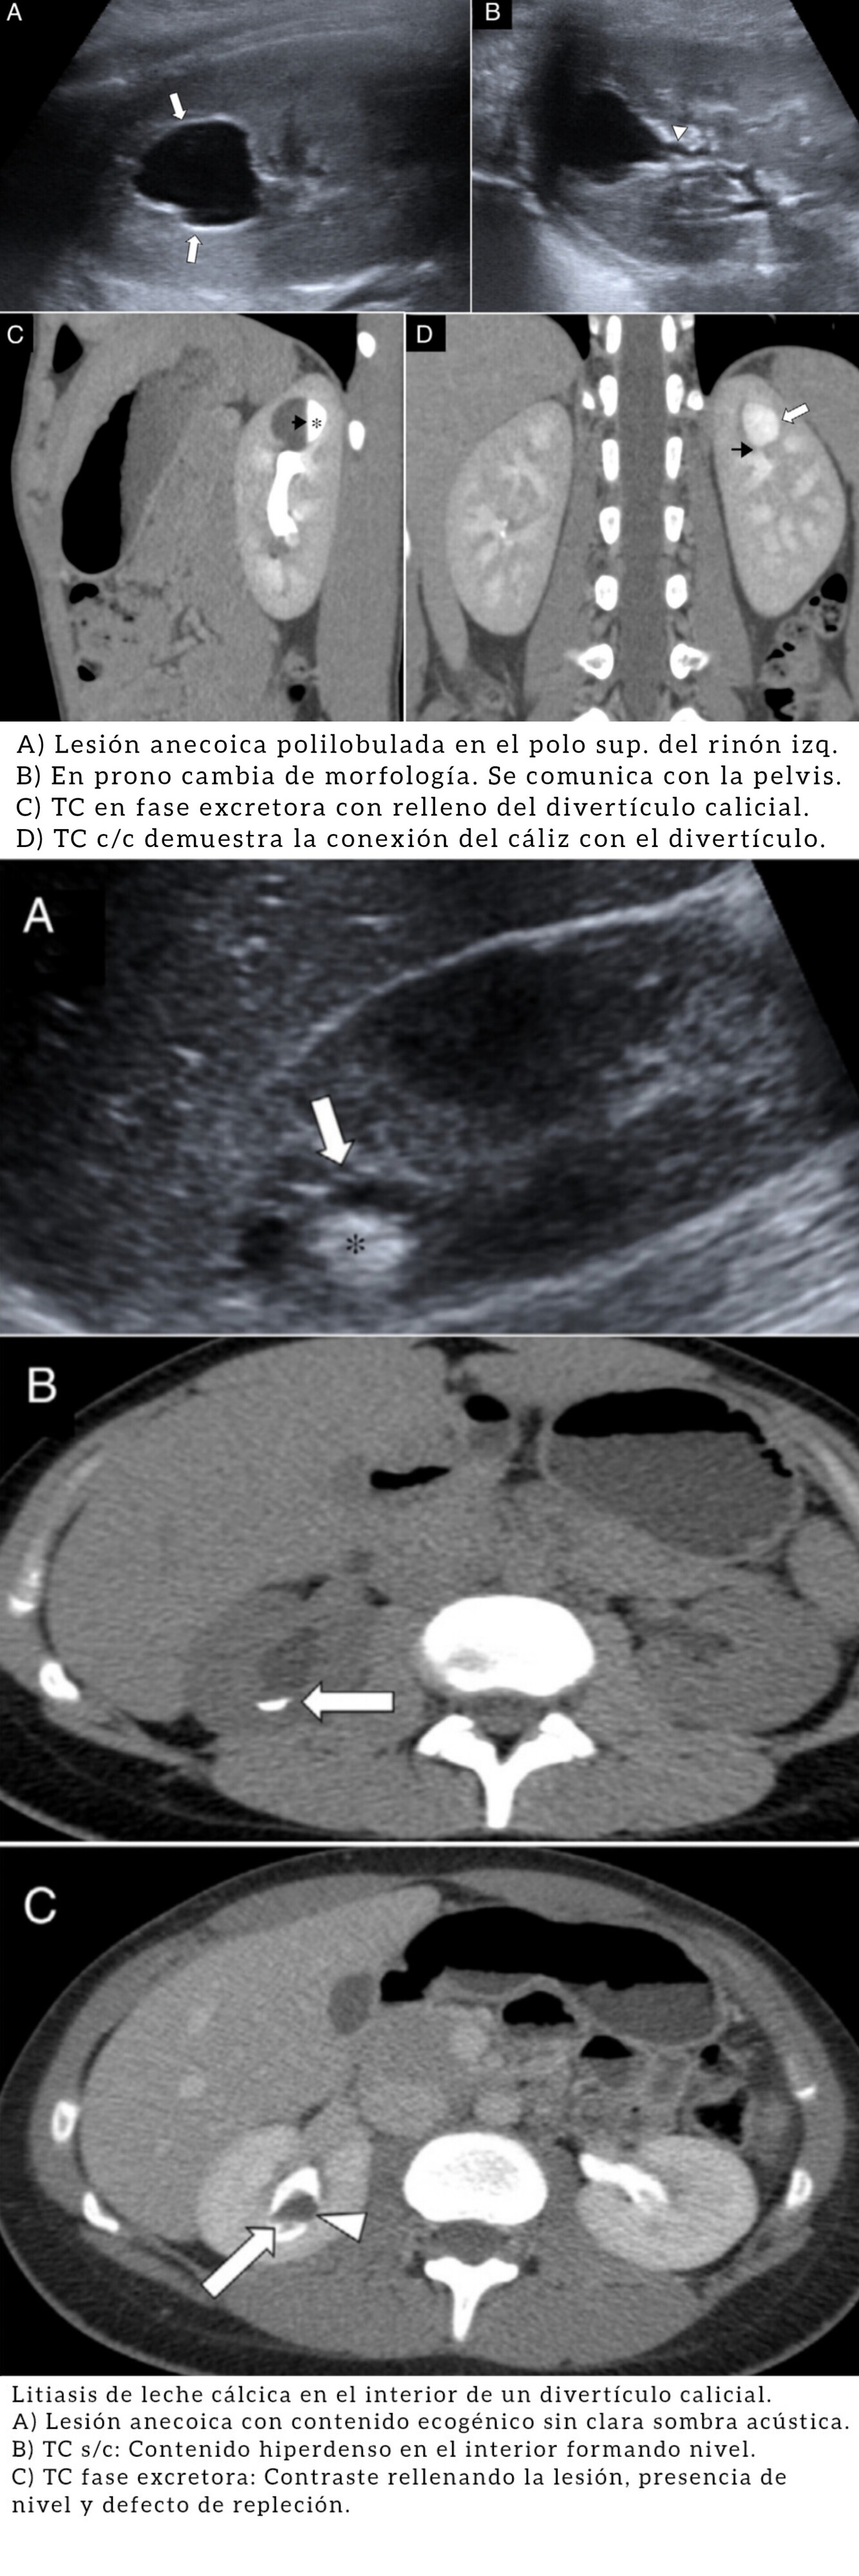

Divertículo Calicial.

Eventración quística intraparenquimatosa tapizada por epitelio celular transitorio con una estrecha conexión infundibular con los cálices o pelvis (término más exacto es divertículo pielocalicial).

Infradiagnosticado por confundirse con quistes; el dg confirma con

TC/RM) en fase excretora.